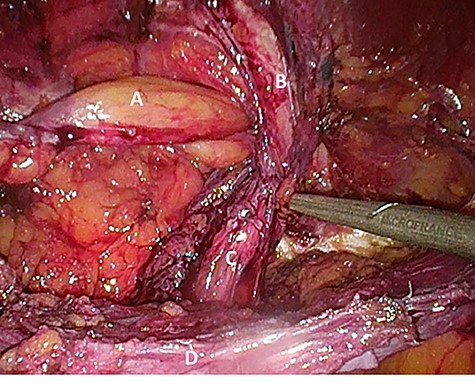

Considering the patients’ comorbidities (obesity, Type 2 diabetes mellitus), a re-TAPP was performed to avoid possible wound complications. The recurrent hernia was presumably confirmed as a lateral inguinal hernia. After dissecting dense fibrotic scar tissue around the previous mesh preperitoneally, the hernia sac was released. A large spermatic cord lipoma was found and dissected (Figs 1 and 2). A new mesh (BARD® 3D Light Mesh, 10 × 15 cm) was inserted.

Suspected indirect inguinal recurrence hernia with a large spermatic cord lipoma (A), epigastric vessels (B), ductus deferens (C), peritoneum with previous mesh (D).